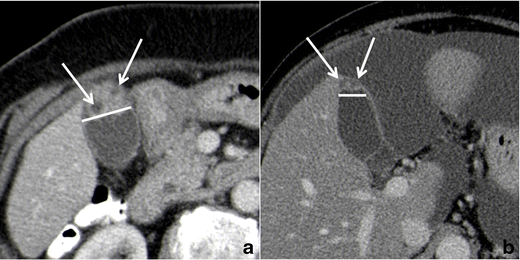

Well-delimitated hypodense intramural spaces, representing RAS, can be confidently recognized only if they reach 3–4 mm in diameter and if they have a clear bile content (Fig. 13). If RAS are clearly identified, CT diagnosis of GA can be made.

Fig. 13

Gallbladder adenomyomatosis: typical CT findings. At CT, gallbladder adenomyomatosis is characterized by mural thickening (line) containing cystic spaces representing Rokitansky–Aschoff sinuses (arrows). Large RAS can be easily identified on 3-mm-thick reconstructions (a), whereas for identifying smaller RAS thin slices evaluation is crucial (b)

CT images evaluation using thin slice thickness (1–2 mm) increases accuracy in identifying RAS and in excluding extramural infiltration, although it shows more background noise compared to thicker reconstructions.